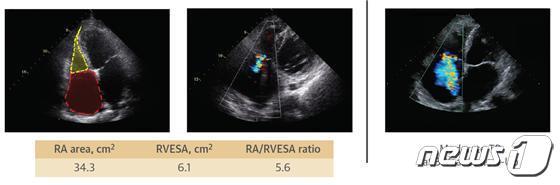

또한 심장초음파 지표 중 우심방 크기가 클수록 심방 기능성 삼첨판막 역류증이 발생할 위험이 높은 것으로 나타났다.

특히 우심실 크기에 비해 우심방이 더 뚜렷하게 확장된 경우에 심방 기능성 삼첨판막 역류증이 호발하는 것으로 확인됐다.